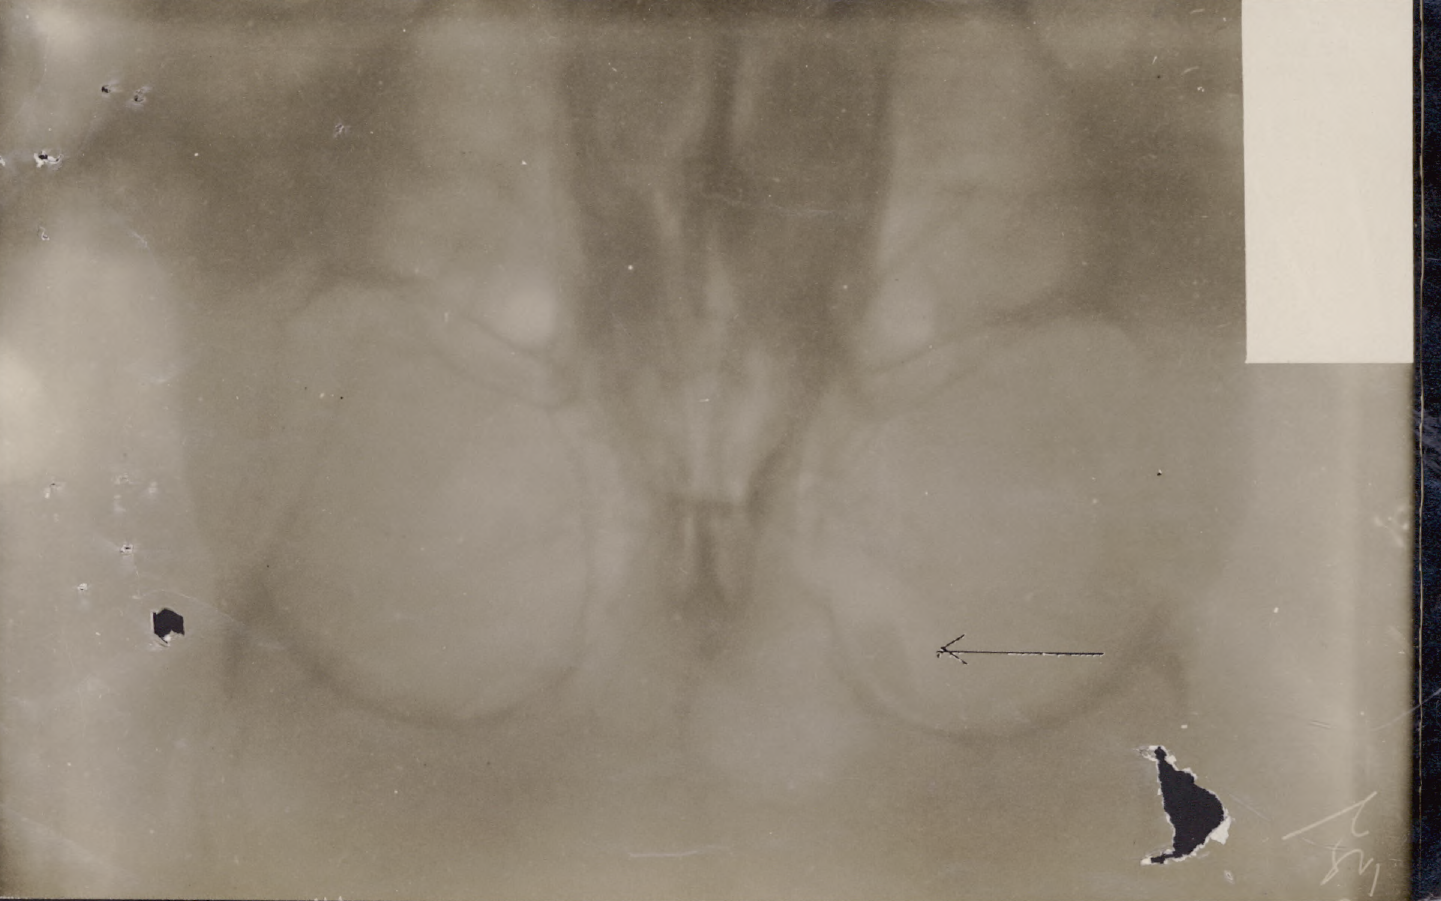

Shunk, Reginald Alexander: Service no. 775381 Digitized Service Record Source: Per news clipping post by David Archer on the 18th Battalion Facebook Page (not group). Find-A-Grave Shunk, Reginald: Service no. 775381. Source: Toronto Telegram. March 1917. Per news clipping post by David Archer at 18th Battalion Facebook Page (not group). X-rays of wound. Share this: Email a link to a friend (Opens in new window) Email Share on Facebook (Opens in new window) Facebook Share on X (Opens in new window) X Share on Reddit (Opens in new window) Reddit Share on LinkedIn (Opens in new window) LinkedIn Print (Opens in new window) Print Share on Tumblr (Opens in new window) Tumblr Share on Pinterest (Opens in new window) Pinterest Share on Telegram (Opens in new window) Telegram Share on WhatsApp (Opens in new window) WhatsApp Like Loading...